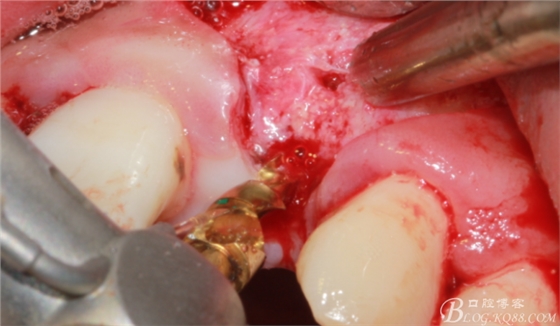

徹底搔刮拔牙窩,偏腭側(cè)備洞

順利植入植體,扭力30N。三壁骨,感覺美美的。